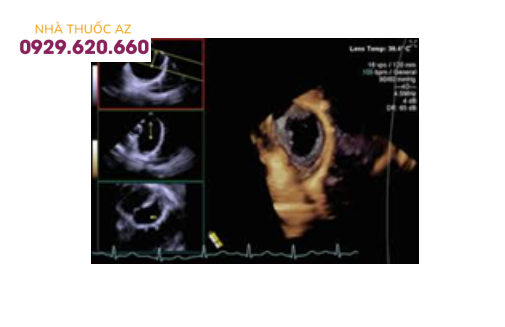

Thông liên nhĩ kích thước lớn trên siêu âm 4D (3 hình đen trắng nhỏ bên trái là siêu âm 2D qua thực quản, từ đó dựng thành hình 4D)